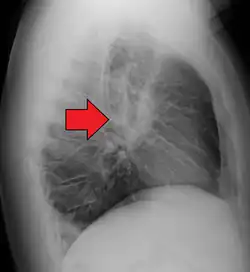

| Chest X-ray showing the typical nodularity of sarcoidosis, predominantly in the hila of the lungs. | |

Hilar adenopathy especially on the person's left (lateral CXR) -